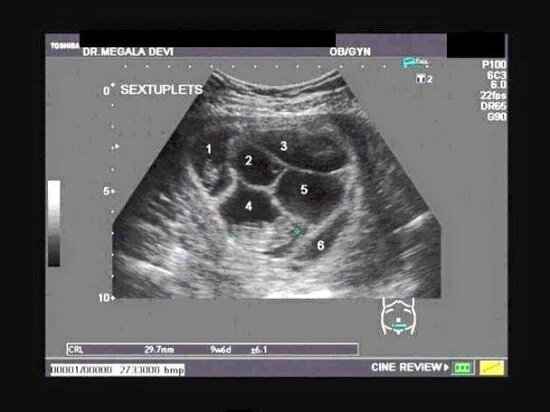

Pierwsze badanie u lekarza pokazało, że poziom hCG jest zbyt wysoki, co mogło świadczyć o ciąży bliźniaczej.

Była to bardzo dobra wiadomość dla małżeństwa. Tak długo próbowali zajść w ciążę, że informacja o ewentualnych bliźniaczkach ich uszczęśliwiła. Wszystko miało się wyjaśnić po badaniu USG.

Lekarz w trakcie badania USG był oszołomiony.

„Drodzy moi, spodziewacie się pięcioraczków!” – oznajmił.

Za chwilę jednak dodał:

„Przepraszam, widzę szóste dziecko!”